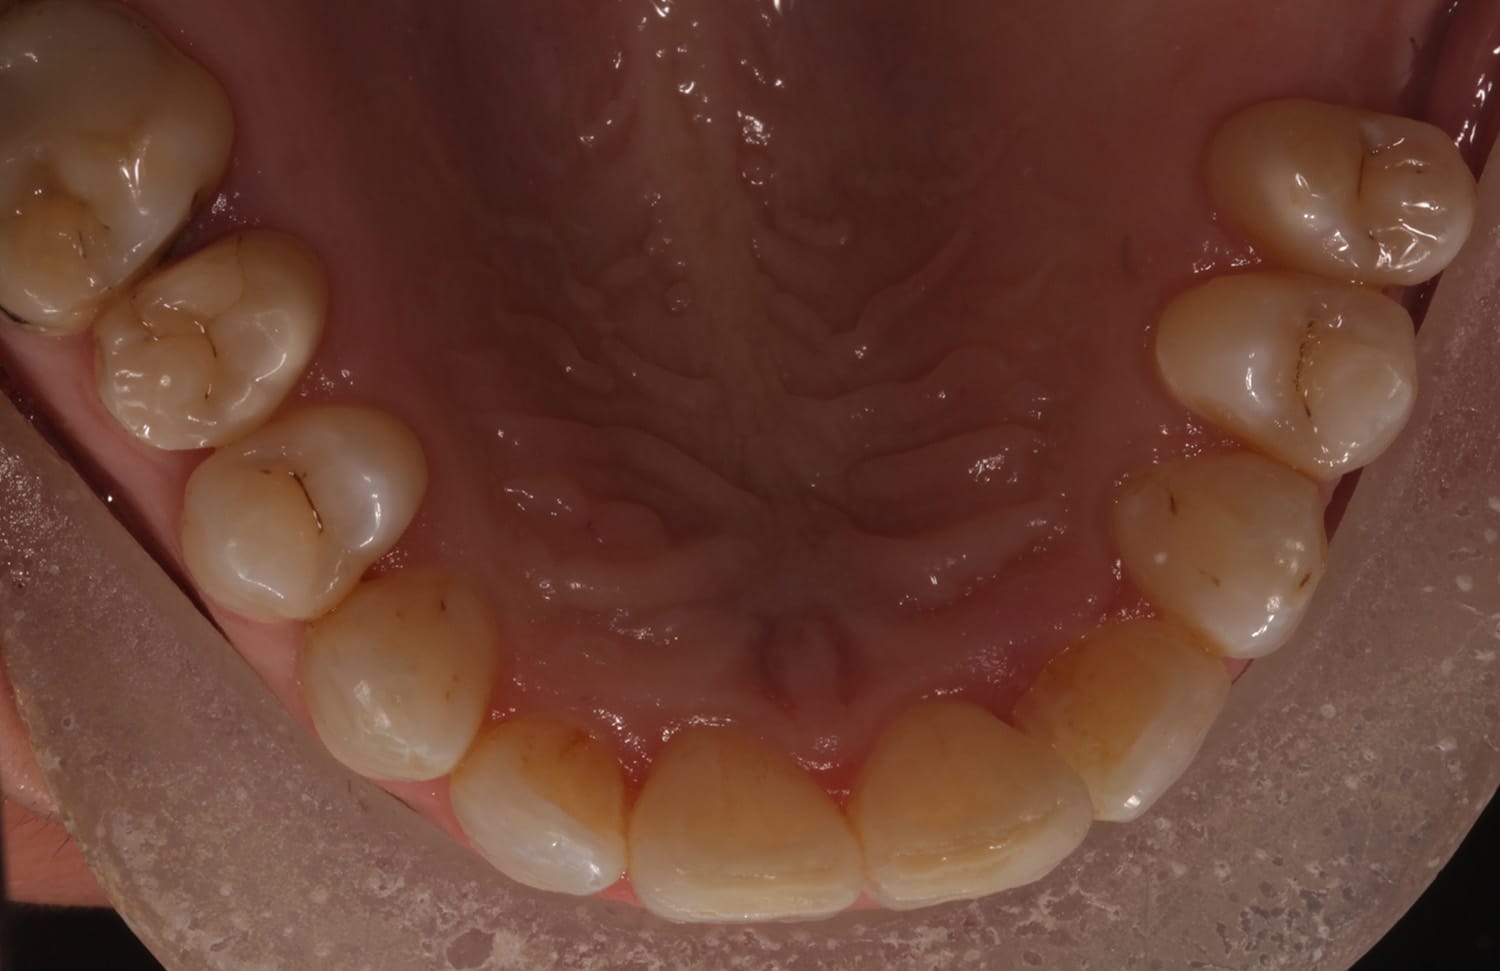

Invisalign is a discreet and reliable way to move your teeth. In general, straighter teeth are easier to look after, so your chances of maintaining a higher level of oral hygiene are improved if you undergo this treatment. If you have straighter teeth, it will usually be easier for your dentist to provide a higher standard of dentistry with better treatment outcomes.

(Treatment time : 8 months)